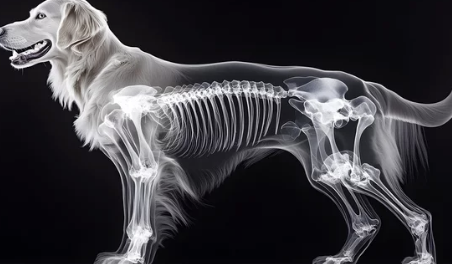

강아지들도 나이가 들거나 특정 질환이 있으면 관절염이 생길 수 있습니다. 움직임이 둔해지고 아파하는 모습을 보면 보호자 입장에서는 정말 가슴이 아프죠. 강아지 관절염은 조기 발견과 적절한 치료로 삶의 질을 크게 개선할 수 있습니다. 오늘은 강아지 관절염의 원인부터 치료법, 관리 방법까지 꼼꼼히 알아보도록 할게요.

강아지 관절염은 관절에 염증이 생겨 통증과 움직임 제한을 유발하는 질환입니다. 특히 나이가 들수록 발병 가능성이 높아지며, 소형견보다는 대형견에게 더 흔히 발생합니다.